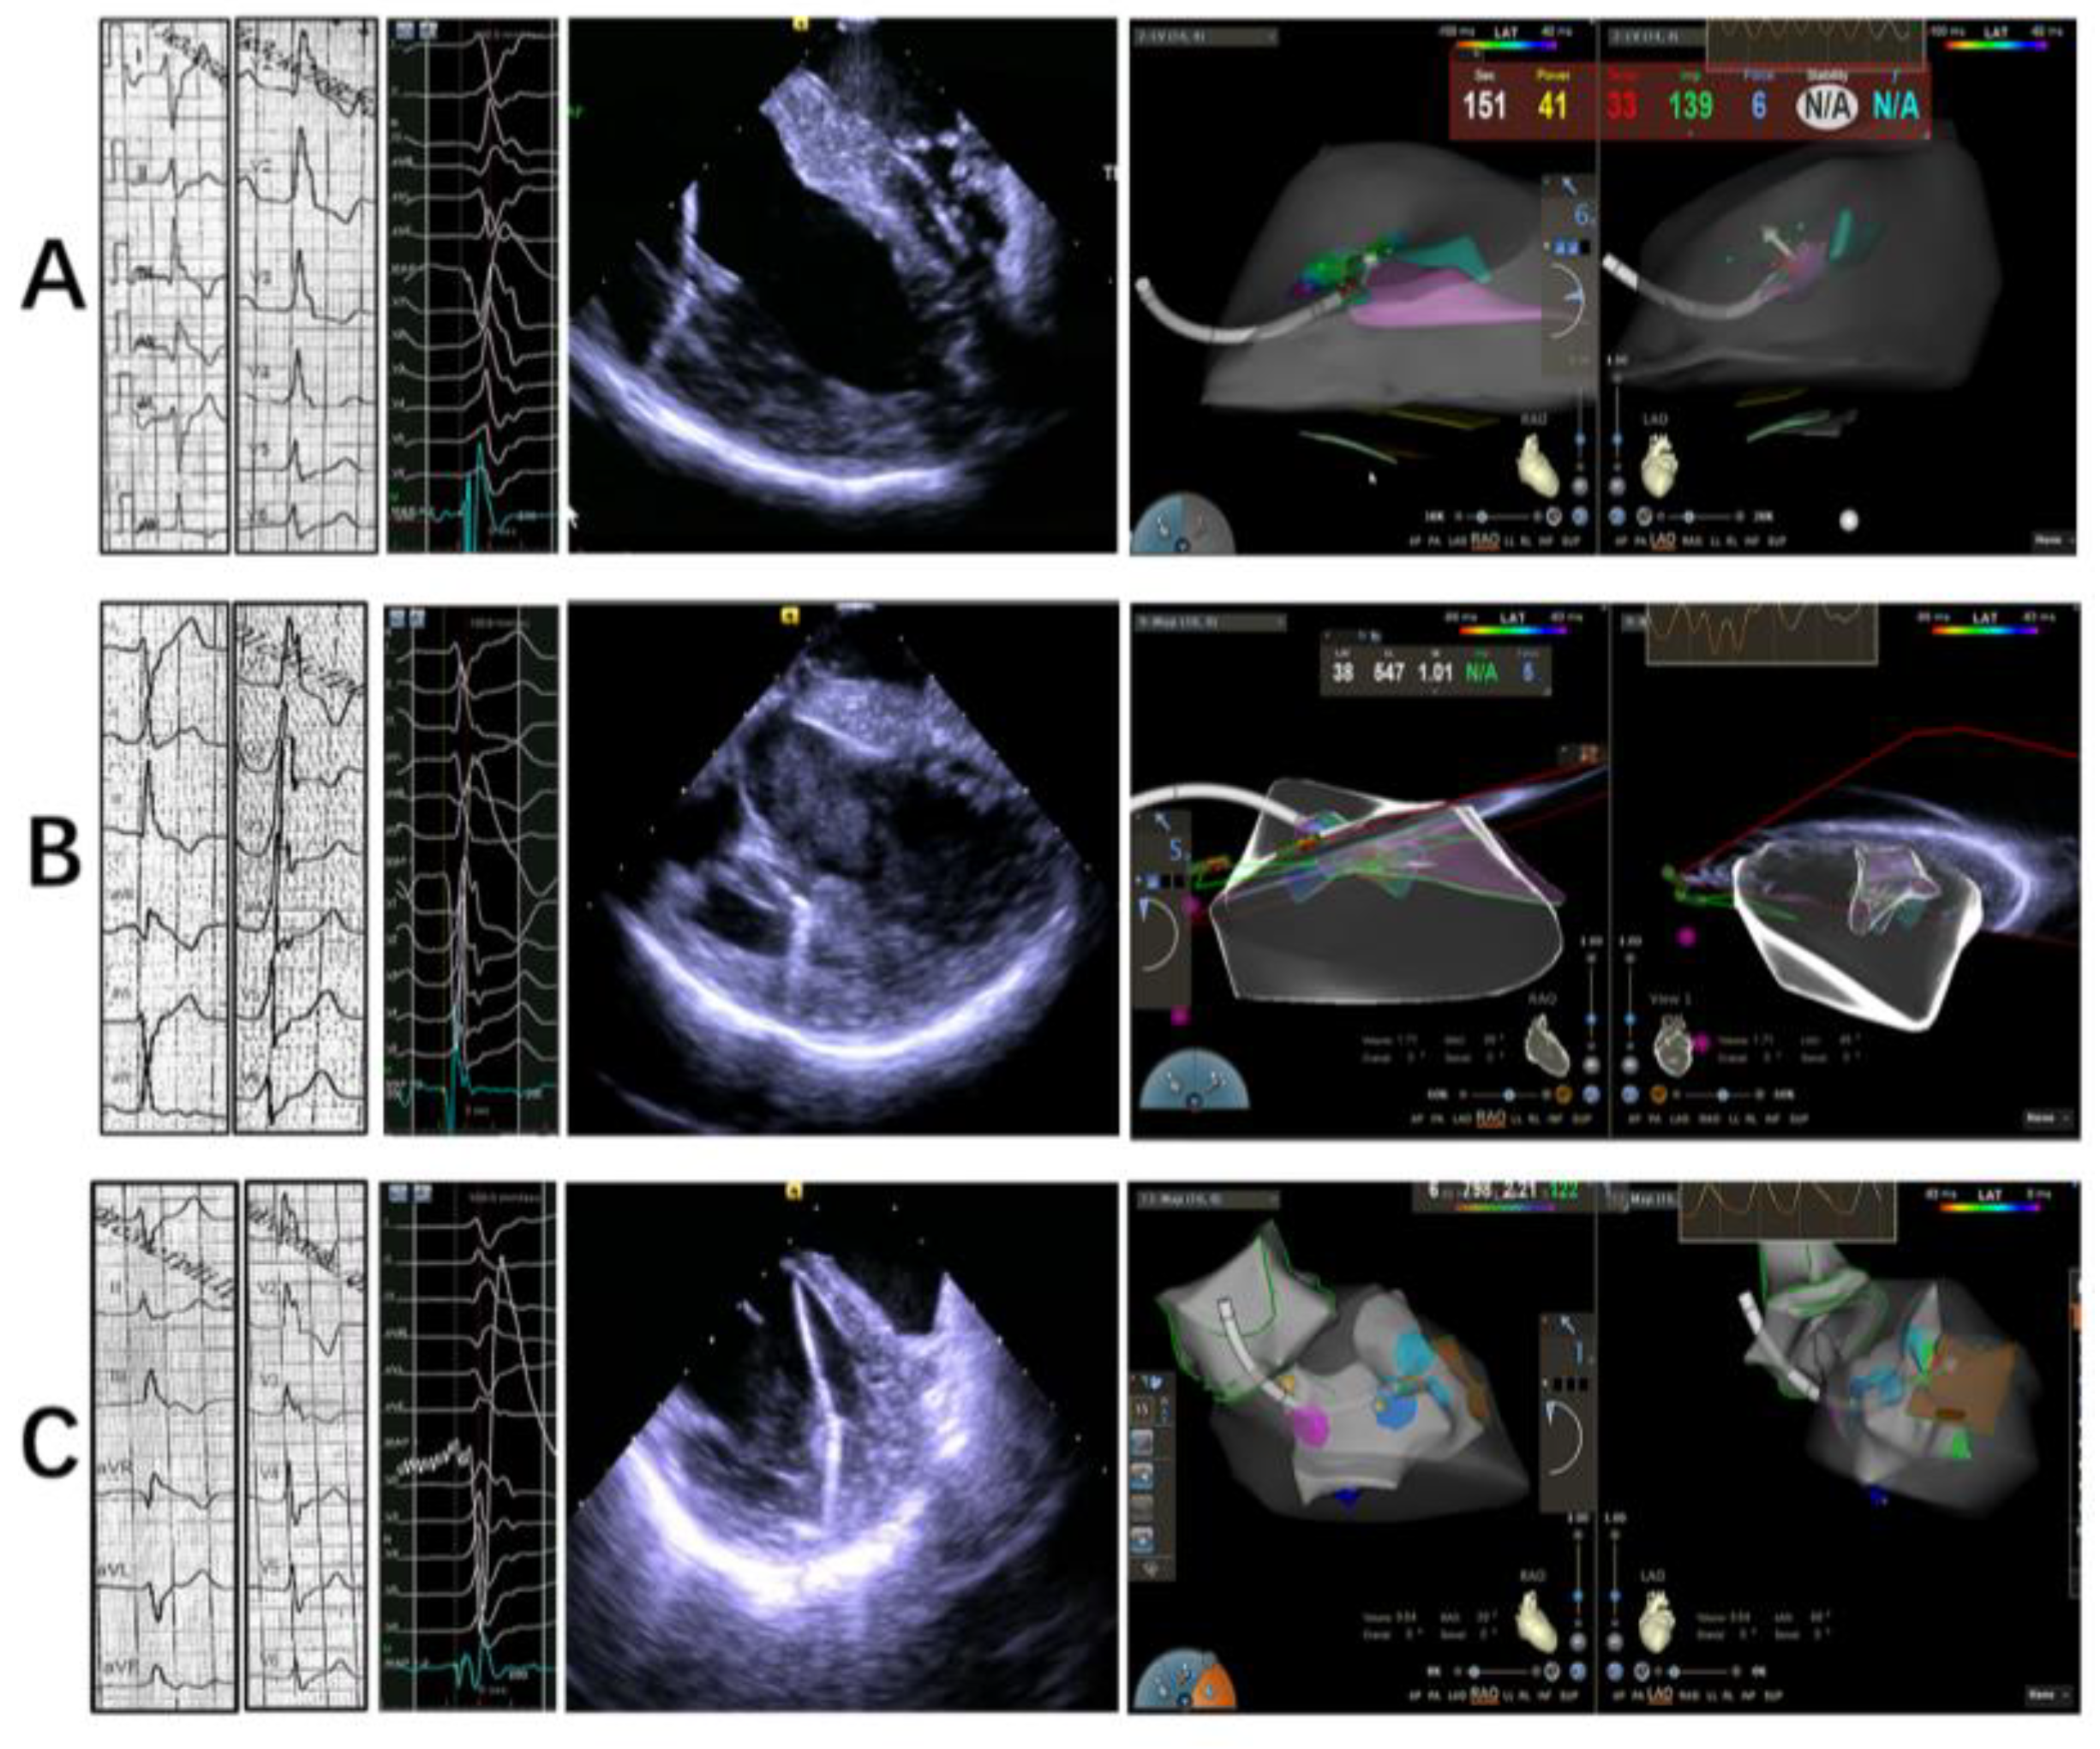

2.2. Electrophysiology Study, Mapping and Ablation

2.2.1. Intracardiac Echocardiography

2.2.2. Mapping and Ablation